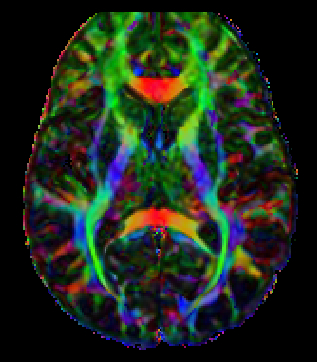

One of the most significant hurdles in treating mild traumatic brain injury (TBI) is that standard MRI scans frequently return "normal" results despite patients experiencing persistent, life-altering symptoms. The research highlighted in this episode explains that by oversimplifying patient groups, we often obscure the meaningful characteristics of brain injuries. By utilizing more sensitive sequences like diffusion tensor imaging, researchers can finally see the structural white matter changes that validate what veterans have been saying for years.

A key takeaway from the study is that the mechanism of injury determines the physical signature left on the brain. Blast exposures tend to impact the central white matter of the brain due to the unique physics of the pressure wave. In contrast, repetitive impact injuries often show changes in more peripheral gray matter structures. Understanding these differences allows clinicians to move away from a "one size fits all" approach and toward more accurate, personalized care.